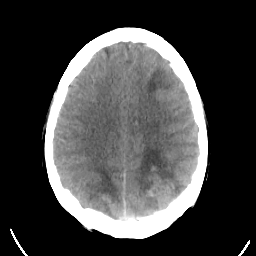

Sarcoma: Roentgen-ray CT -- Slice #17

[Home][Help][Clinical] Slice 17